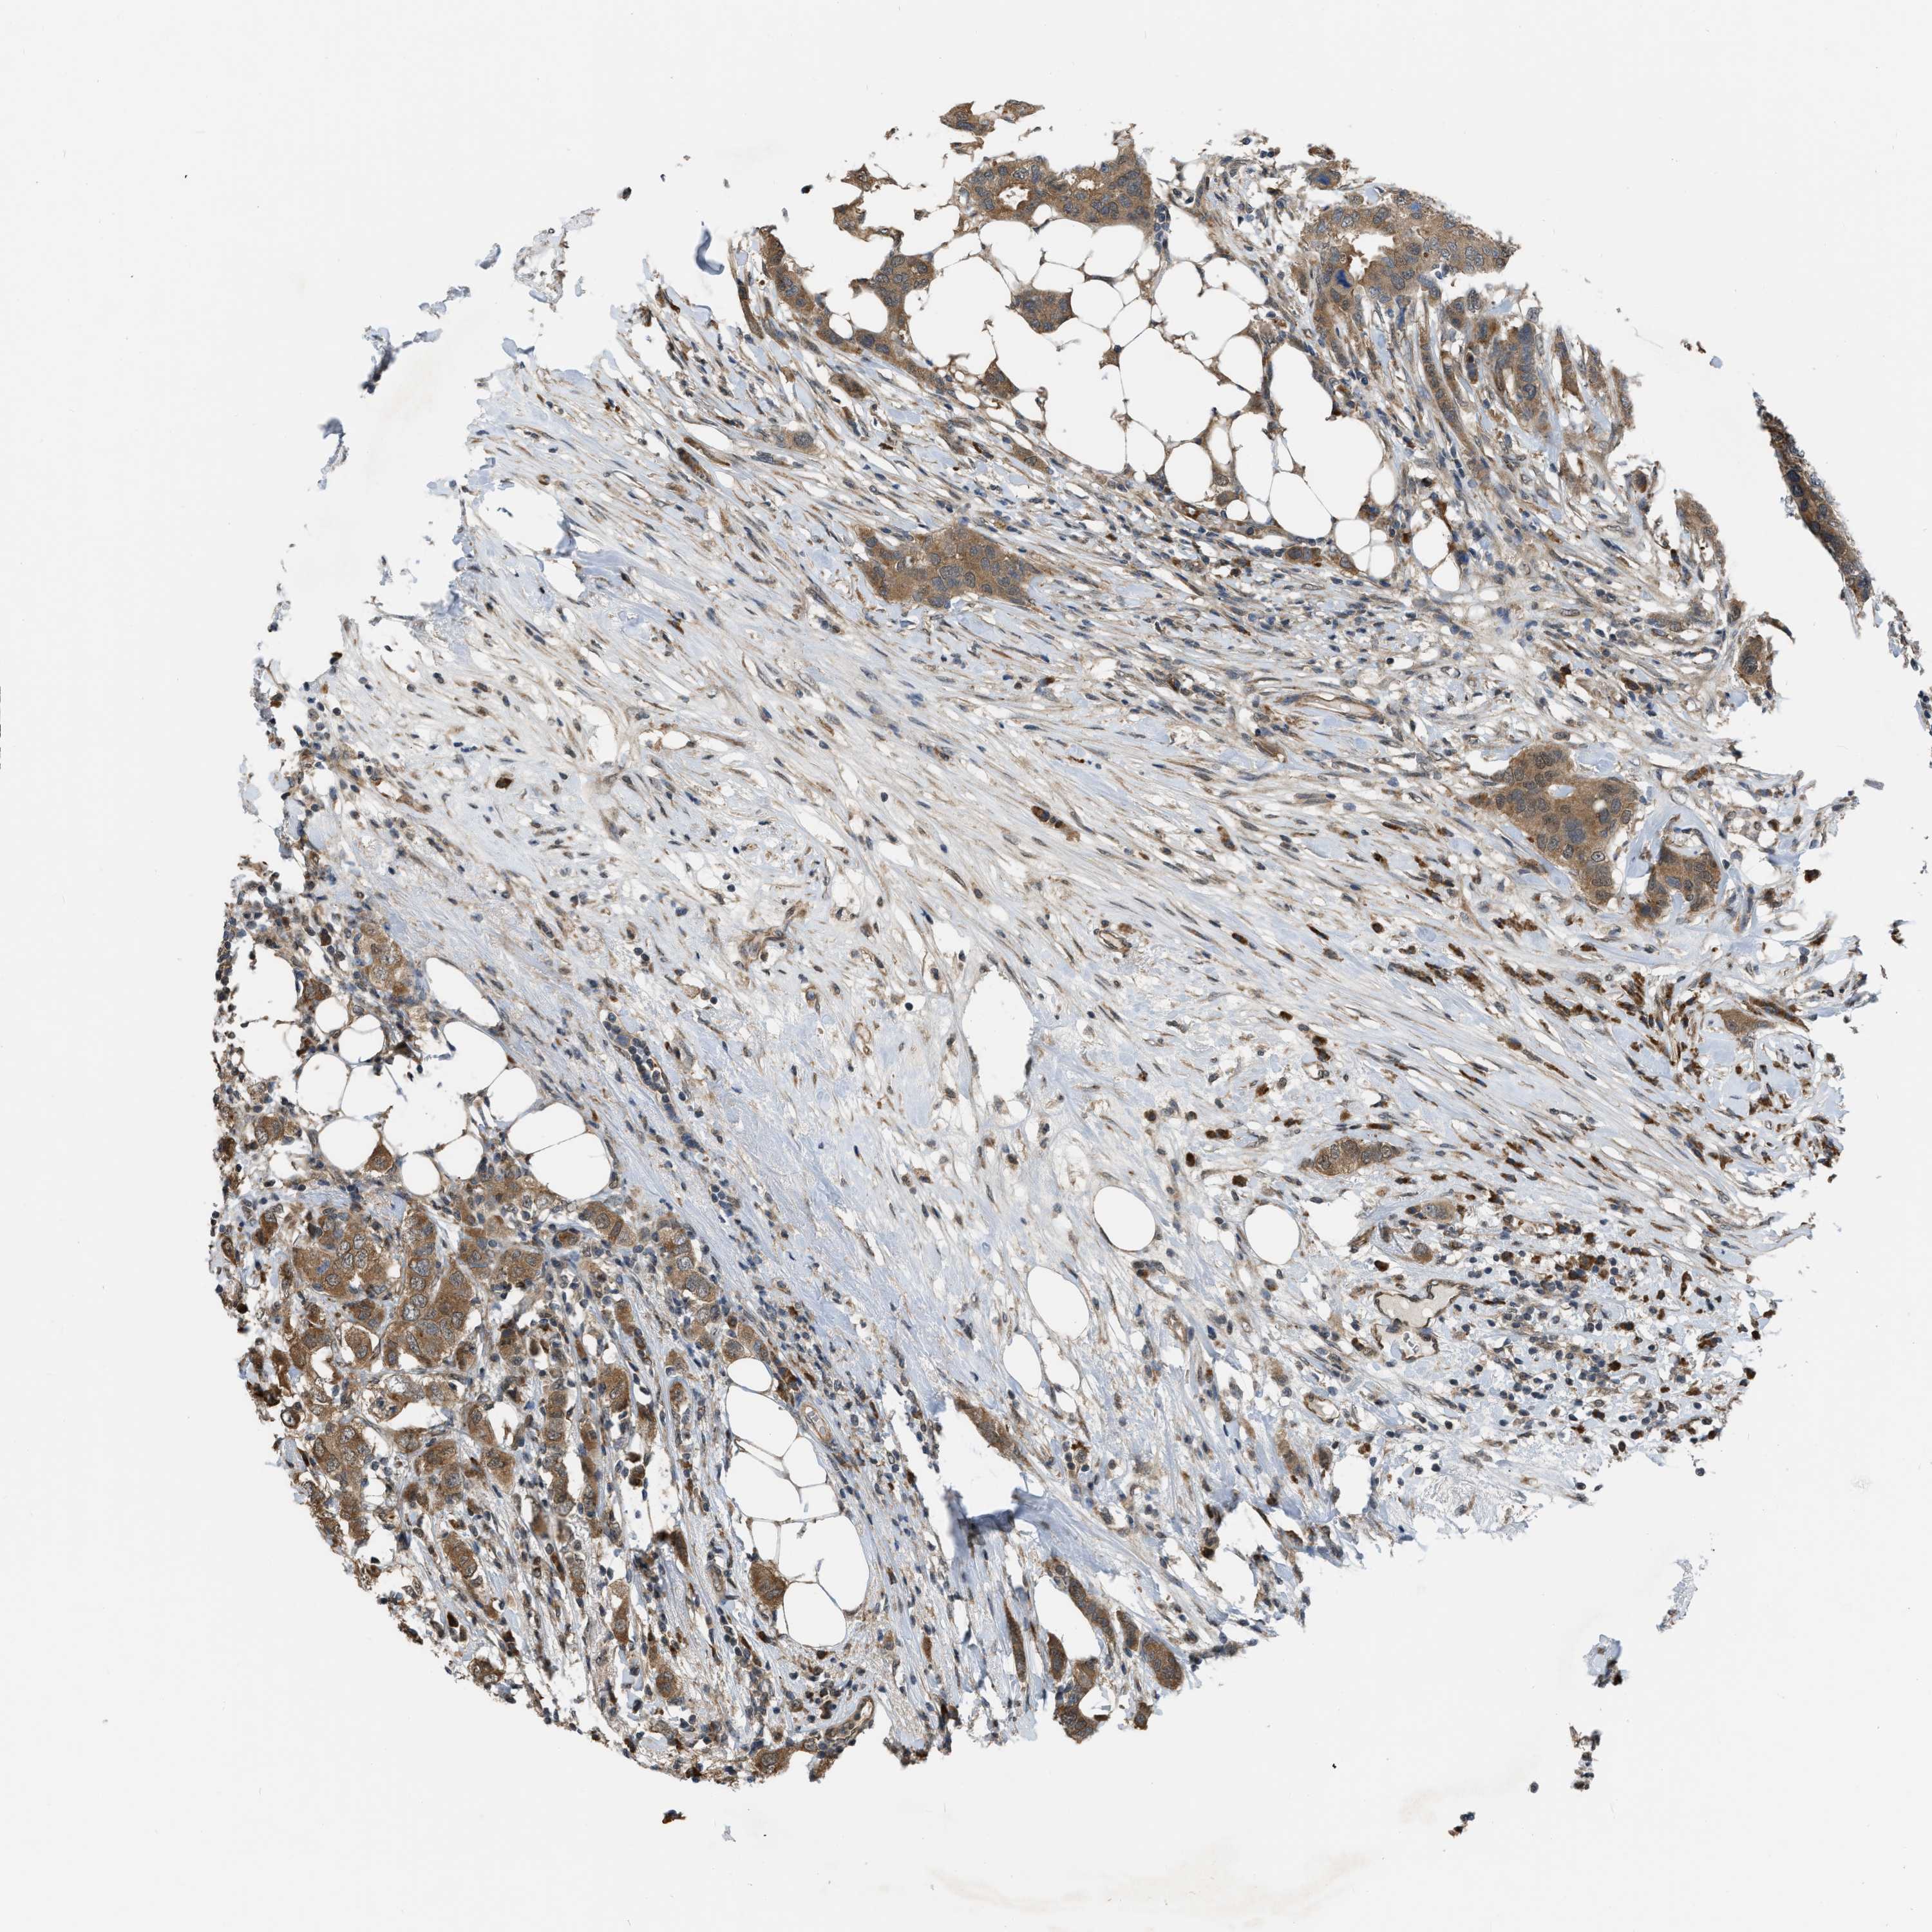

BRCA TCGA BRCA VALIDATION PROTEIN EXPRESSION